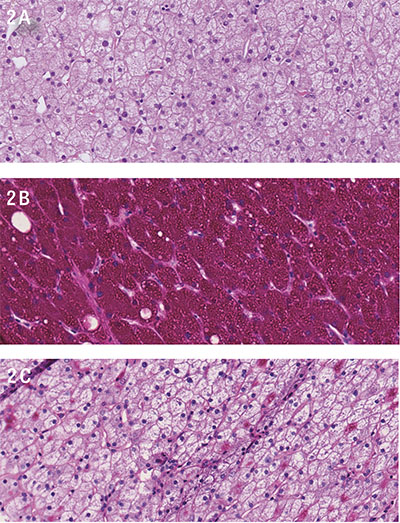

För att utesluta avflödeshinder i levervener och portakretslopp gjordes DT buk som inte kunde påvisa något sådant; däremot en uttalad hepatomegali (Figur 1), men inga tecken till steatos eller andra parenkymförändringar.

Figur 1. Uttalad hepatomegali hos patienten. Datortomo­grafisk bild (A: axialt, B: sagittalt) som visar kraftigt för-

storad lever, cirka 22,5 cm kraniokaudalt utan synliga förändringar i leverparenkymet.